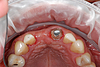

L'aménagement des tissus gingivaux dans le cadre des traitements implantaires

Un implant est envisagé pour remplacer une incisive perdue, mais le volume de gencive résiduelle est trop faible.

Une greffe de gencive concomitante à la pose de l'implant permet de retrouver un volume de gencive adéquat.